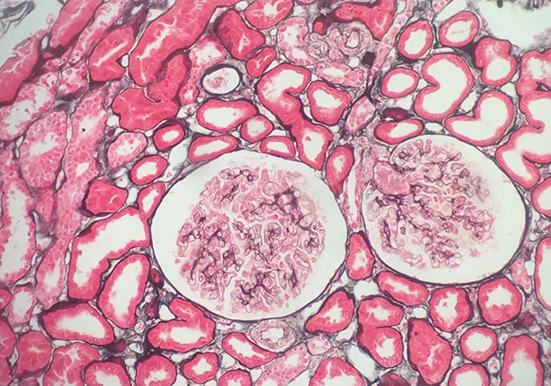

刚果红染色

刚果红染色是一种常用的生物染色方法,以下是关于它的详细介绍:基本信息染料性质:刚果红是一种经典的酸性染料,化学式为 C32H22N6Na2O6S2,是一种棕红色粉末,能溶于水和乙醇。染色原理:主要依赖于其与蛋白质及其他生物大分子的亲和性,通过静电吸引、氢键等作用力与样品中的不同组分发生相互作用,使样品呈现出特定的颜

刚果红染色是一种常用的生物染色方法,以下是关于它的详细介绍:

染料性质:刚果红是一种经典的酸性染料,化学式为 C32H22N6Na2O6S2,是一种棕红色粉末,能溶于水和乙醇。

染色原理:主要依赖于其与蛋白质及其他生物大分子的亲和性,通过静电吸引、氢键等作用力与样品中的不同组分发生相互作用,使样品呈现出特定的颜色。